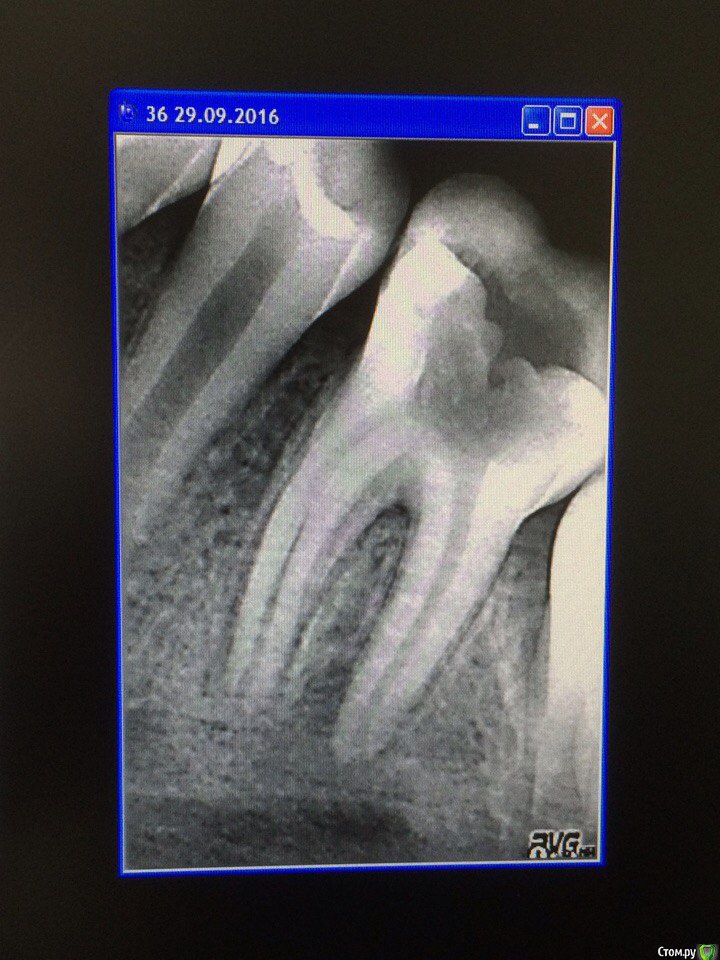

Wrestrus66 Опубликовано 29 сентября, 2016 Поделиться Опубликовано 29 сентября, 2016 Всем доброй ночи , Зуб 36 лечен в другой клинике...По словам родителей : жалобы на перкуссию и ночные боли Зуб вскрыли потекло рекой гнойное отделение ( каналы не прошли вскрыли до устьев и на полоскание )Вопрос: как дальше быть , а точнее про ростковую зону можно уже забыть?или же делать эндо гх,эдта и кальций?!вопрос на сколько оставлять кальции и ждать ил апексогенеза? Ссылка на комментарий

crown Опубликовано 29 сентября, 2016 Поделиться Опубликовано 29 сентября, 2016 Только не апексогенез а апексефикация препаратами кальция, зоне роста конец при периодонтите. Протокол как у взрослых. Да кстати открытый зуб ухудшает прогноз. 1 Ссылка на комментарий

Wrestrus66 Опубликовано 2 октября, 2016 Автор Поделиться Опубликовано 2 октября, 2016 Только не апексогенез а апексефикация препаратами кальция, зоне роста конец при периодонтите. Протокол как у взрослых. Да кстати открытый зуб ухудшает прогноз.показывает ли апекс в неср каналах да ещё и Pt ?! проста тут главное за апекс никакой гадости не вывести.. Да и мех и мед обработка на всю длину надо отступишь 05 1мм считай будет рецидив.. Кто сталкивался с таким случаем как четко определить длину к/к Ссылка на комментарий

crown Опубликовано 2 октября, 2016 Поделиться Опубликовано 2 октября, 2016 Да постоянно сталкиваемся. Возьмите файл по-жирнее 40, 45 тогда апекс будет показывать. Зачем рецидив? Коффер, эндомотор, гипохлорит, эдта, кальций и герметичная реставрация - irm, фото и все прекрасное заживет. Ссылка на комментарий

crown Опубликовано 3 октября, 2016 Поделиться Опубликовано 3 октября, 2016 На водной основе каждый месяц, масляные 3 -6 месяцев Ссылка на комментарий